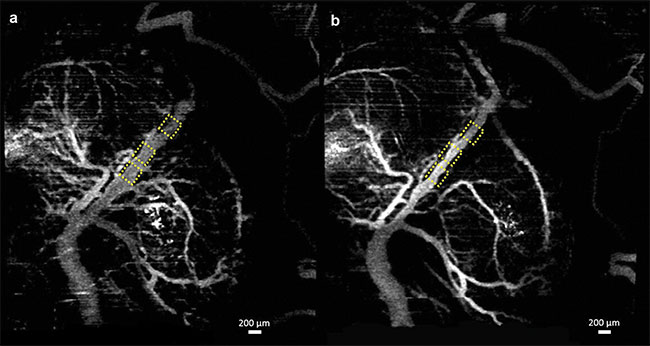

Figure 2. Vasculature changes in the embryonic brain before (a) and 45 min after (b) maternal exposure to nicotine. Adapted with permission from Reference 11.

In recent studies, angiographic OCT was used to image murine fetal brain vasculature in utero10-12. A series of experiments documented changes in murine fetal brain vasculature minutes after maternal exposure to various drugs. Embryos of pregnant mice at embryonic day 14.5 were imaged. This period corresponds to the end of the first trimester and beginning of the second trimester in human development. Initial OCT imaging was performed, and the mother was administered the drug for the corresponding study. Subsequent measurements were taken of the embryo for a period of 45 min, at 5-min intervals.

For the nicotine experiments, nicotine at a dose of 1 mg/kg was used. This dose in mice is known to cause intrauterine growth restriction. Both the alcohol and nicotine were administered via intragastric gavage. For the SCB studies, CP-55,940 at a dose of 2 mg/kg, suspended in a compound of dimethyl sulfoxide (DMSO) (Alkamuls El 620: lactated Ringer’s solution at a ratio of 1:1:18), was sprayed onto the liver of the mother. CP-55,940 was used because it is a well-known and well-characterized compound in SCB research.

Speckle variance OCT (svOCT) and correlation mapping optical coherence angiography (cmOCA) are two types of angiographic OCT techniques that were used in the studies. While svOCT calculates the variance between multiple images taken at the same spatial location, cmOCA calculates the correlation coefficient between the images to capture any dynamic scatterers (such as blood in this case) in the specific location. These procedures are followed at multiple consecutive locations to obtain a vasculature map. Once the 3D vasculature maps were obtained, the maximum intensity projections (MIPs) were calculated to obtain 2D images.

Figures 1-3 show the vasculature in the fetal brain before and after maternal exposure to ethanol, nicotine, and SCBs, respectively.

In all three cases, when compared to placebo groups, a drastic reduction in vessel diameter was observed within 45 min of maternal exposure, demonstrating the possibility that all three teratogens act as a vasoconstrictor on the fetal brain. Such constriction could have a drastic effect on normal brain development.